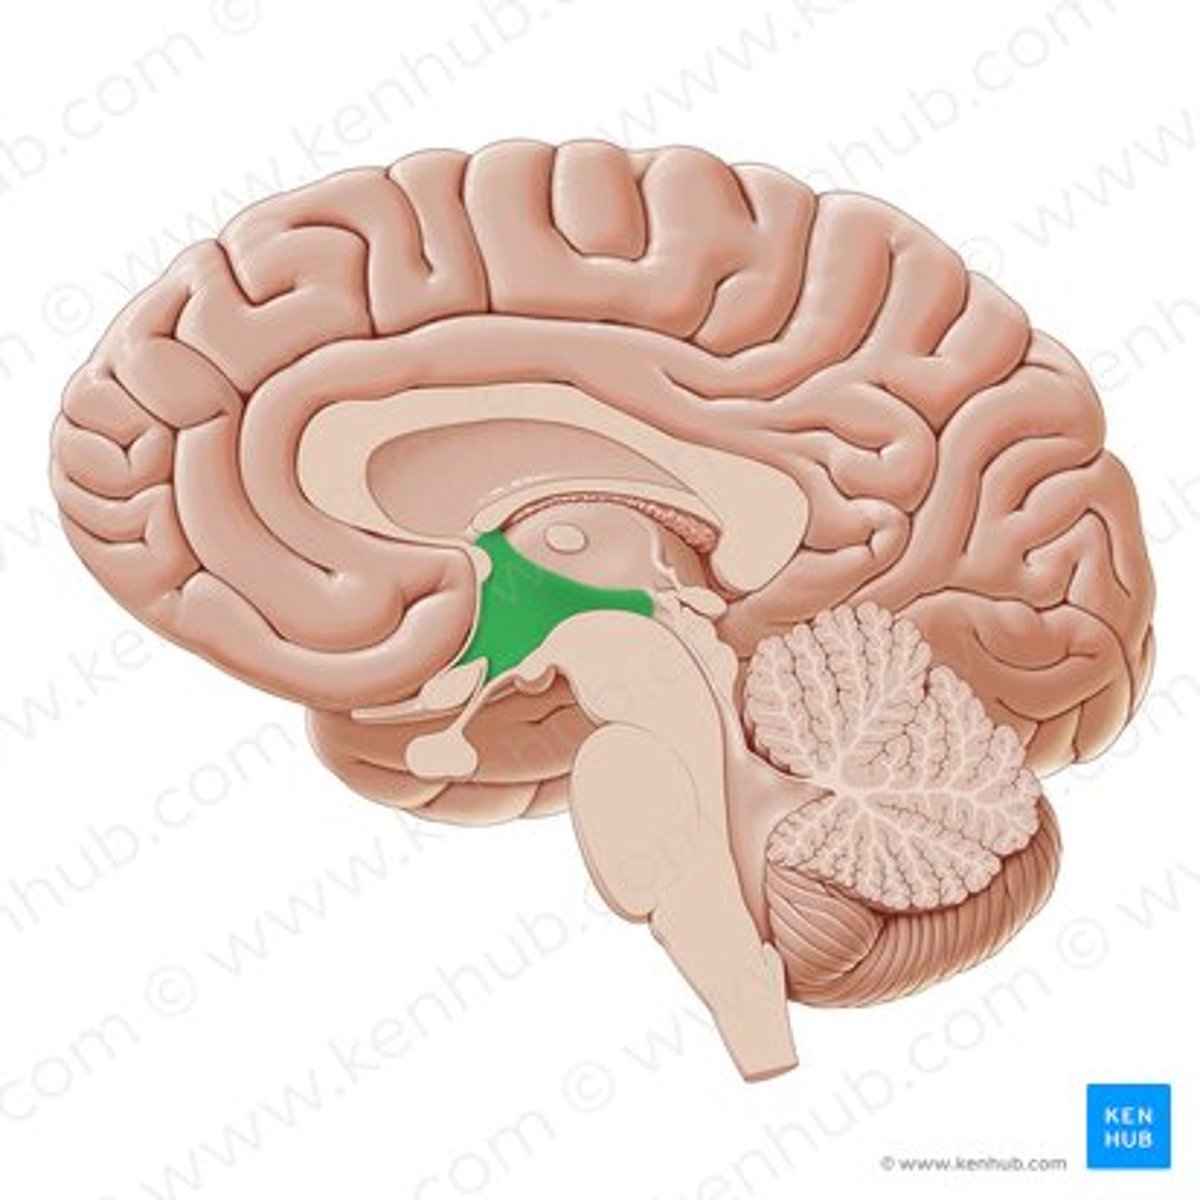

third ventricle